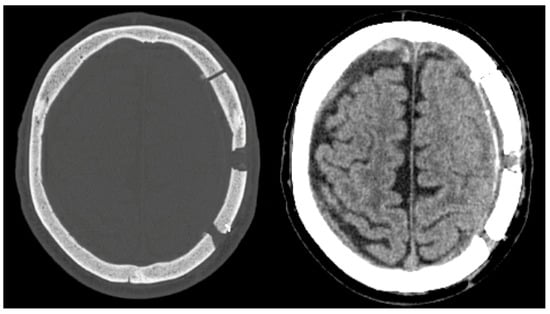

Unfortunately, 18 days after discharge, the patient developed a seizure disorder and showed right-sided hemiparesis and incomplete aphasia, resulting in a hospital readmission. The CT scan revealed progression of the left-sided cSDH with the flattening of the gyration and, thus, was seen as symptomatic (Figure 1A). A reexamination of the head CT revealed that a 71.8 mL cSDH had returned. The patient was taken to the operating room and underwent burr-hole trepanation and hematoma evacuation. However, due to the firm hematoma, no subdural drain placement was achievable, and the post-op CT scan revealed a postoperative subarachnoid hemorrhage (Figure 1B).

After the patient showed no clinical improvement, we identified an indication for revision surgery by means of craniotomy and hematoma evacuation, which was performed using the herein-introduced endless-loop craniotomy technique. Details of the surgical steps are displayed in the next section. Because of the vulnerable cortex and an already-present postoperative hemorrhage, we chose a non-watertight dura closure, and an epidural Jackson-Pratt drain was left for 2 days (Figure 1C,D). Figure 2 shows an illustration of the two different surgical techniques in a sagittal CT scout: burr-hole (A) and endless-loop craniotomy (B). The detailed operative steps for craniotomy, dura opening, and drain management are shown in Figure 3 and Figure 4. The operation was performed as planned without intraoperative complications.

Figure 1. (A,B): Pre- and post-burr-hole CT scans after left-sided cSDH evacuation in axial and coronal views. (C,D): Different window settings after revision surgery with endless-loop craniotomy and the placement of a Jackson-Pratt drain. The yellow horizontal line on the coronal slices shows the axial level.